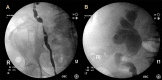

Malakoplakia is a chronic inflammatory condition that affects multiple systems, most commonly the urogenital tract. Its clinical presentation is often non-specific, but is typically characterized by recurrent urinary tract infections and haematuria. We report a rare case of intravesical malakoplakia mimicking an aggressive transitional cell carcinoma both in its clinical presentation and in its macroscopic appearance on cystoscopy in an 82-year patient, the oldest reported case in the literature. Malakoplakia has been described in the literature as a benign disease process presenting typically in younger patients. This case demonstrates its ability to cause obstructive uropathy and affect elderly patients. Thus, this case serves as a reminder to consider malakoplakia as a differential in the evaluation of suspected bladder malignancy in patients of all ages.